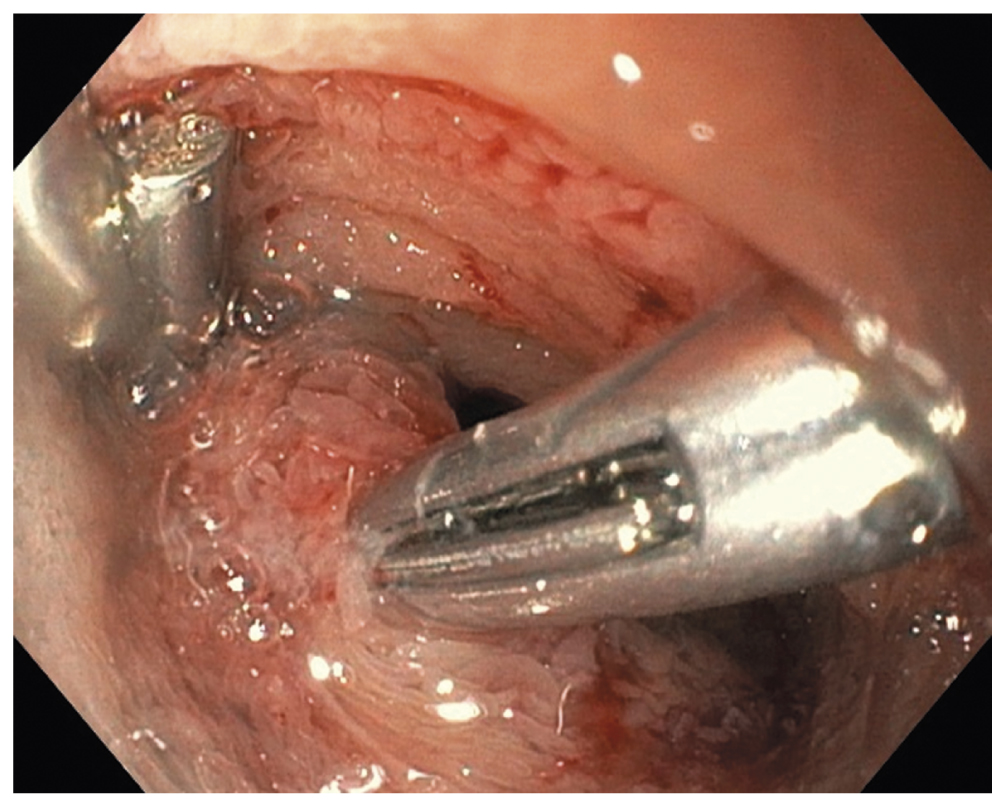

Рис. 8. Эпителиальное новообразование захвачено эндоскопической петлёй

Fig. 8. An epithelial lesion is taken by an endoscopic snare

Поскольку в день операции у ребёнка был отмечен очередной эпизод мелены, для исключения поражений Дьелафуа, а также для осмотра тощей кишки на уровне расправленного тонкокишечного инвагината (30–40 см от связки Трейтца) интраоперационным консилиумом принято решение выполнить третье эндоскопическое исследование верхних отделов ЖКТ. В положении ребёнка на левом боку под СО2-инсуффляцией с применением ручного пособия тонкий видеогастроскоп заведён в тощую кишку, где на расстоянии около 40 см от пилорического канала было обнаружено эпителиальное новообразование шаровидной формы размерами 15×17 мм на короткой широкой ножке толщиной около 6 мм (тип 0-Ip по Парижской классификации эпителиальных новообразований) (рис. 6). Поверхность полипа гиперемирована, покрыта единичными округлыми эрозиями с налётом фибрина. Новообразование легко смещалось в просвете кишки при помощи инструментальной пальпации. С целью расширения возможностей инструментария тонкий видеогастроскоп заменён на аппарат стандартного диаметра с рабочим каналом 2,8 мм, который с техническими трудностями, обусловленными малым диаметром просвета ЖКТ у ребёнка, был проведён к новообразованию. Первым этапом с помощью эндоскопического инъектора выполнено введение в подслизистый слой физиологического раствора с индигокарминовым красителем в основание полипа с целью создания гидравлической подушки между слизистой и мышечной оболочками стенки кишки (рис. 7). Отмечен умеренный лифтинг новообразования. Эндоскопической серповидной петлёй Olympus Snare Master 25 мм выполнен захват полиповидного образования в пределах неизменённых тканей и затягивание петли на ножке образования (рис. 8). Выполнено удаление полипа в пределах неизменённых тканей в смешанном режиме коагуляции-резания (электрохирургический блок Olympus) методикой эндоскопической резекции слизистой оболочки. При осмотре после резекции признаков резидуальных тканей новообразования и глубокого повреждения стенки кишки не определялось. Отмечено подтекание крови из ложа удалённого образования. Выполнен гемостаз и сведение краёв дефекта слизистой при помощи трех эндоскопических клипс (рис. 9). Полип извлечён при помощи эндоскопического сачка из просвета ЖКТ и направлен на морфологическое исследование (рис. 10, 11).